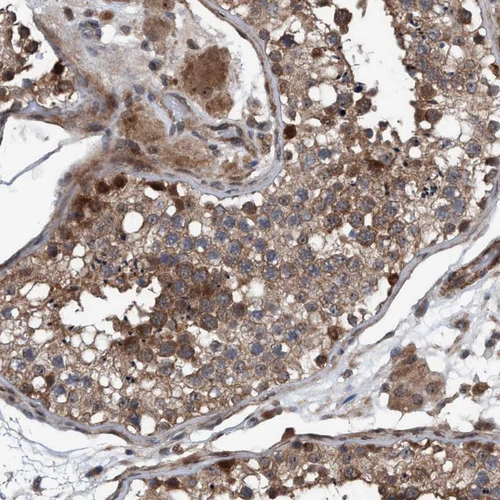

Immunohistochemical staining of human cerebellum shows strong cytoplasmic and membranous positivity in Purkinje cells.